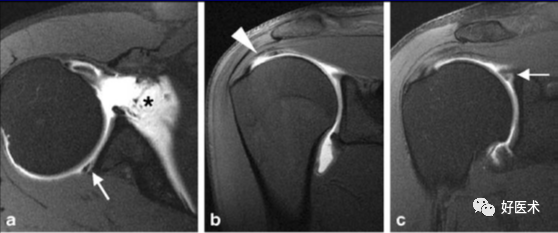

3)完全性撕裂

原发征象:肌腱局部缺如,连续性液体信号横贯肌腱的全层,这使得盂肱关节和肩峰下滑囊相通。

继发征象:

①肩峰下滑膜囊积液,积液在T1WI /PDWI上呈中等信号,T2WI+FS上呈高信号;

②冈上肌肌肉、肌腱结合处回缩(正常位置在肱骨头上方);

③滑囊旁脂肪垫的渗出丢失。

MR 关节造影:局限性或弥漫性充满造影剂的裂隙贯穿肌腱全层,肌腱失去其连续性。

冈上肌肌腱损伤(撞击),肩胛下滑囊积液(肩胛下肌腱损伤?)

冈上、下肌腱撕裂、肩胛下囊积液